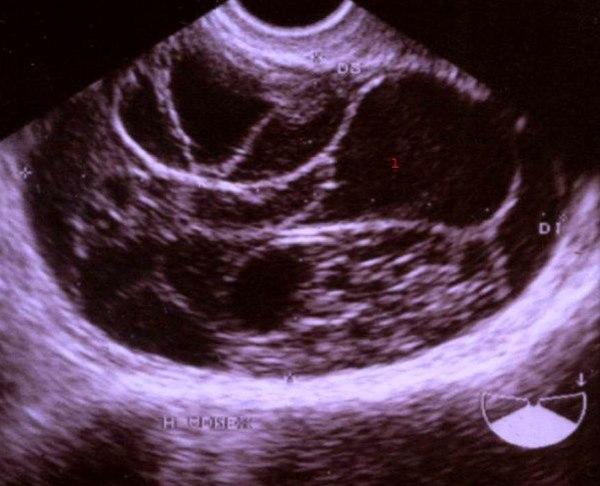

Mucinøst cystadenom (ultralydbilde)Godartede svulster på eggstokkene (ovariene) er som regel cyster. En cyste er en væskefylt blære som kan ses på overflaten av eggstokken. Ofte er det snakk om flere cyster. Polycystisk ovarialsyndrom (PCO) er dog en egen sykdom som er karakterisert ved mange cyster i eggstokkene, og den omtales annet sted.

En lang rekke forskjellige svulster kan oppstå i eggstokkene. De fleste av disse er cyster. Det skilles mellom svulster som utgår fra eggstokkenes overflate, og svulster som utgår fra det indre av eggstokken. Blant de svulstene som utgår fra overflaten, skilles det mellom serøse (vandige) og mucinøse (slimige) cystadenomer. De serøse cystadenomene utgjør cirka 25 prosent av alle de godartede eggstokksvulstene, og de finnes på begge sider i 20 prosent av tilfellene. Serøse cystadenomer kan bli meget store. Også de mucinøse svulstene kan bli svært store. Noen ganger kan de sprekke og utsæd av slimproduserende celler på bukhinnen kan være utgangspunkt for cyster andre steder i bukhulen. Teratomer utgjør 10 prosent av de godartede eggstokksvulstene og inni disse svulstene kan man finne ulike typer vev.